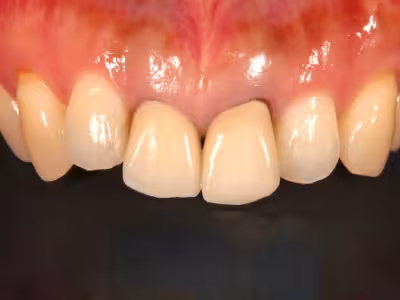

前歯のセラミックス

治療前後写真

治療前

治療後

年齢・性別

50歳・女性

来院理由

前歯の変色・審美障害

治療内容

全体ホワイトニング→失活歯(#11)を再根管治療→#11フルセラミックス修復

#21はレジン充填

治療期間

約3ヶ月

費用

- ホワイトニング 88,000円

- 感染根管治療 121,000円

- セラミック 170,500円

- コンポジットレジン 33,000円

リスク・副作用

歯肉退縮で境目が見える可能性

過度な咬合力でセラミックのチッピング

医院コメント

生物学的安定性を確保した上でセラミックを接着し、色・透明感を自然に調和。